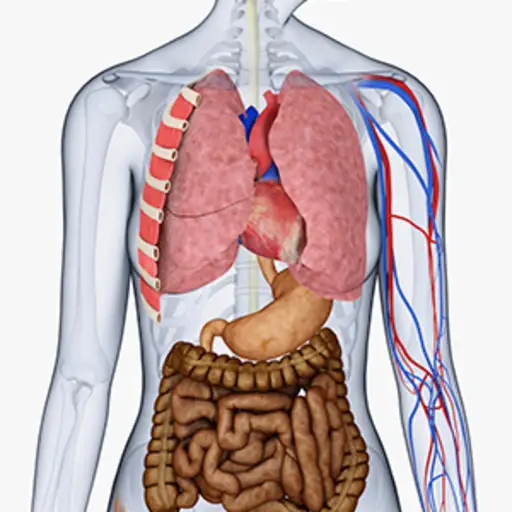

误解6:强直性脊柱炎只是背痛

事实:强直性脊柱炎是一种全身或全身,可影响身体的多个部位的炎性疾病,包括关节和器官。该疾病主要影响脊柱,特别是骶髂关节,但它也可以引起炎症周围关节的疼痛和眼睛,心脏,肺,肾脏和其他器官造成伤害。此外,该疾病可引起显着的疲劳,影响睡眠和认知功能。